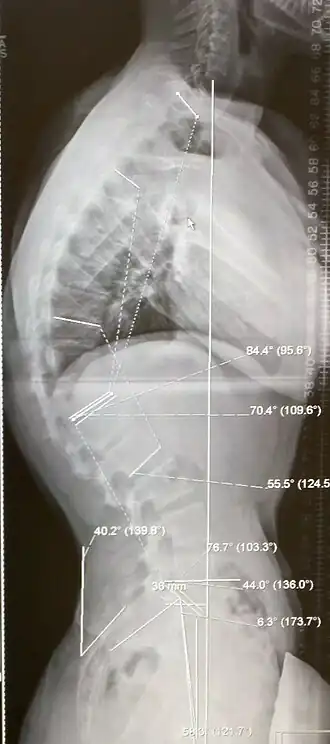

![]() Paciente de 20 años con la enfermedad de Scheuermann, con diversas medidas de la cifosis y la lordosis | ||

La enfermedad de Scheuermann es un trastorno esquelético autolimitado de la infancia. También es conocido como Cifosis de Scheuermann (ya que resulta en cifosis) y cifosis idiopática juvenil de la columna vertebral. Lleva el nombre de Holger Werfel Scheuermann.[1][2][3] La enfermedad de Scheuermann describe una condición en la que las vértebras crecen de forma desigual con respecto al plano sagital; es decir, el ángulo posterior es a menudo mayor que el anterior. Estos resultados del crecimiento desigual en la firma en forma de "cuña" de las vértebras, causando cifosis.

Además del dolor asociado con la enfermedad de Scheuermann, muchas personas que padecen de la enfermedad tienen pérdida de altura vertebral, y dependiendo de donde se encuentra el vértice de la curva, pueden tener una 'joroba' o 'espalda redonda'. Se ha reportado que las curvas en la región torácica inferior causan más dolor, mientras que las curvas en la región superior presentan una deformidad más visual. A pesar de eso, es generalmente el dolor o razones cosméticas que los enfermos buscan ayuda para su condición prontamente. En estudios, la cifosis es mejor caracterizada para la columna torácica que para la columna lumbar.[4][5]